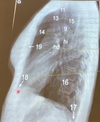

2

3

4

5

Perfectly

Q